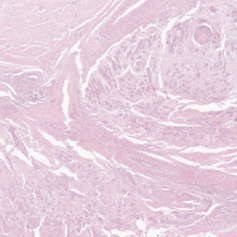

2 Materials

Our experiments were performed on the squamous cell carcinoma (SCC) subset of the publicly available CATCH dataset [11]. Use of these samples was approved by the local governmental authorities (State Office of Health and Social Affairs of Berlin, approval ID: StN 011/20). The specimens were originally digitized with the Aperio ScanScope CS2 (Leica, Germany) at a resolution of using a objective lens. To create a multi-scanner dataset with local correspondences, we digitized the samples with four additional slide scanners (exemplary patches in Figure 1) :

(a) CS2

(b) NZ 210

(c) NZ 2.0

(d) P 1000

(e) GT 450